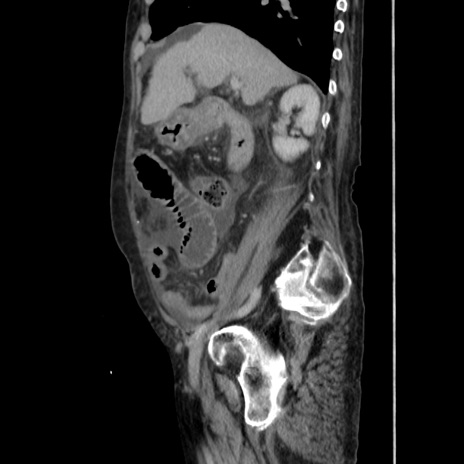

症例31(矢状断像)

【症例】80歳代 女性

【主訴】腹部膨満感

【現病歴】他院にて肝硬変にてフォロー中。1週間前から便秘、腹部膨満感、臍部腫瘤あり受診となる。

【既往歴】肝硬変

【身体所見】腹部膨隆あり、皮膚変化なし、疼痛なし。

【データ】WBC 4600、CRP 0.25